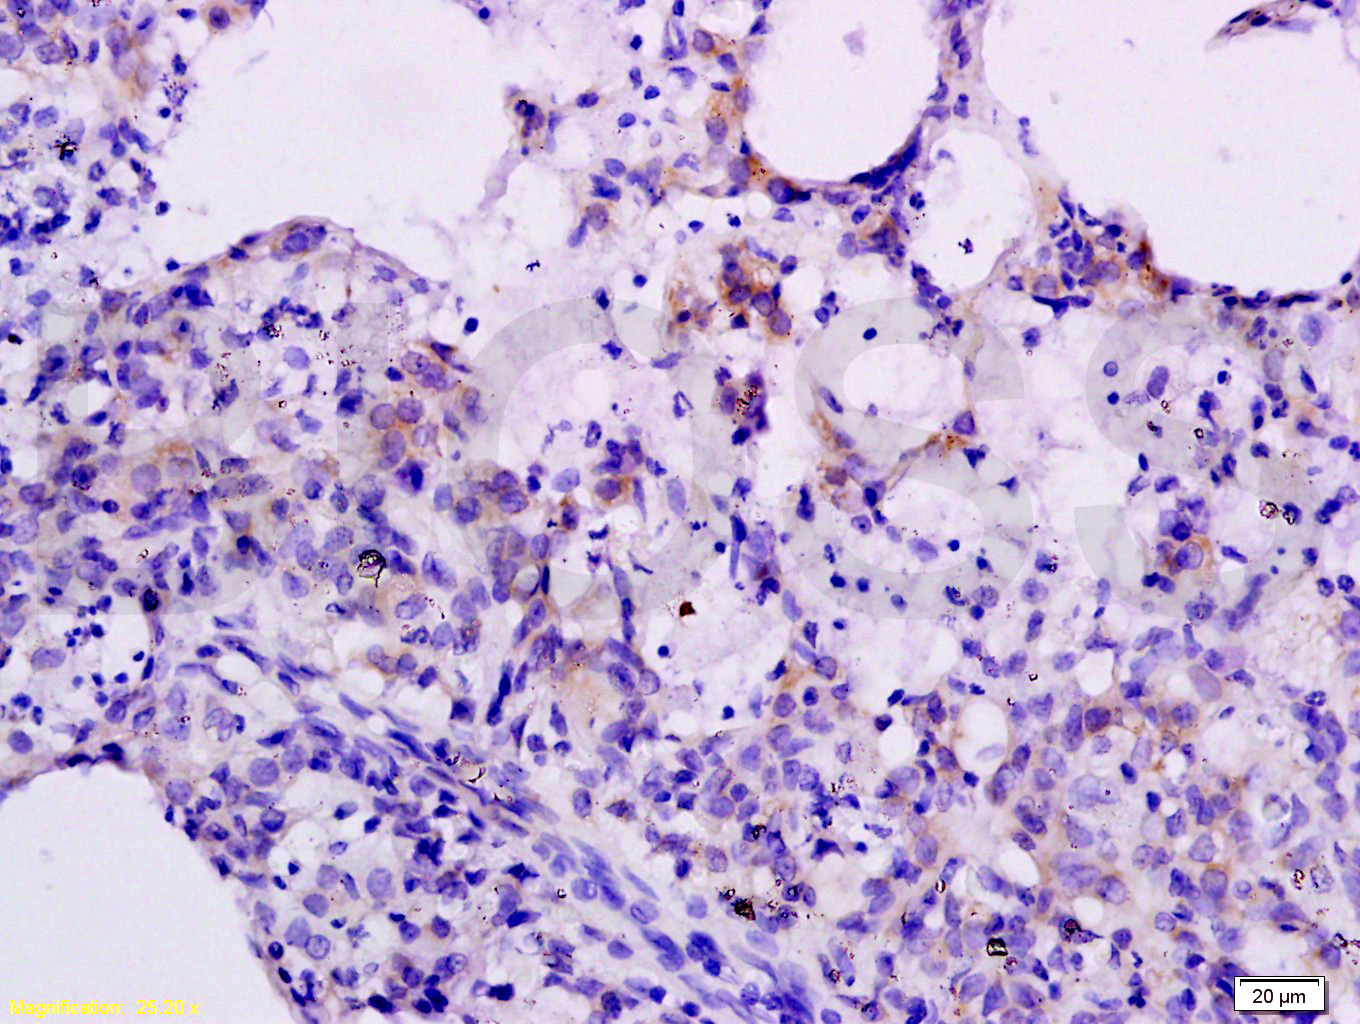

Tissue/cell: rat lung tissue; 4% Paraformaldehyde-fixed and paraffin-embedded; Antigen retrieval: citrate buffer ( 0.01M, pH 6.0 ), Boiling bathing for 15min; Block endogenous peroxidase by 3% Hydrogen peroxide for 30min; Blocking buffer (normal goat serum,C-0005) at 37℃ for 20 min; Incubation: Anti-CXCL10 Polyclonal Antibody, Unconjugated(bs-1502R) 1:200, overnight at 4°C, followed by conjugation to the secondary antibody(SP-0023) and DAB(C-0010) staining